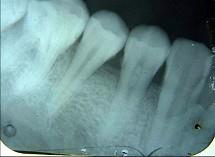

以下哪一项是诊断牙髓钙化的主要手段 ( )A.光纤透照B.电活力测验C.视诊D.温度测验E.X线片检查

问题 以下哪一项是诊断牙髓钙化的主要手段 ( )

选项 A.光纤透照 B.电活力测验 C.视诊 D.温度测验 E.X线片检查

答案 E